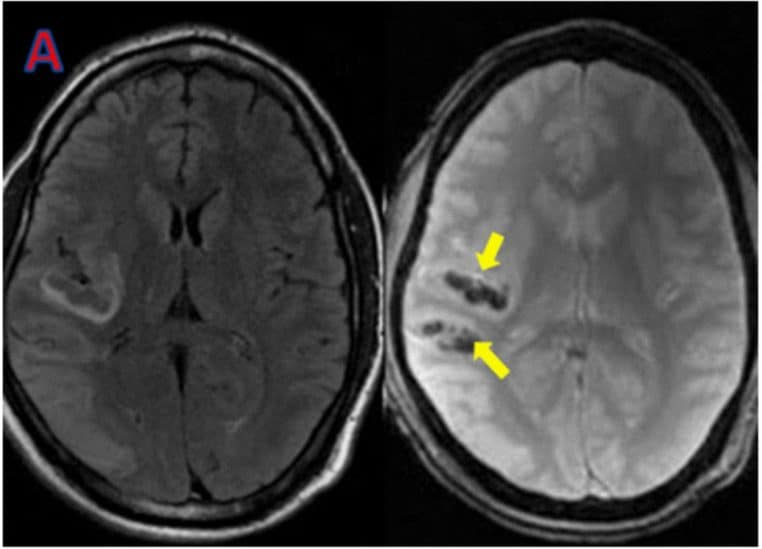

Ce que l’IRM révèle, parfois bien après

Les AVC silencieux laissent des traces typiques visibles en IRM (séquences FLAIR, DWI/ADC ou T2*) : zones d’hyperintensité ou de nécrose témoignant d’un infarctus ancien, parfois multiple. Plus ces traces s’accumulent, plus le risque de troubles cognitifs et de démence vasculaire augmente à long terme. Cela explique pourquoi la prévention vasculaire a un impact direct sur la santé du cerveau.